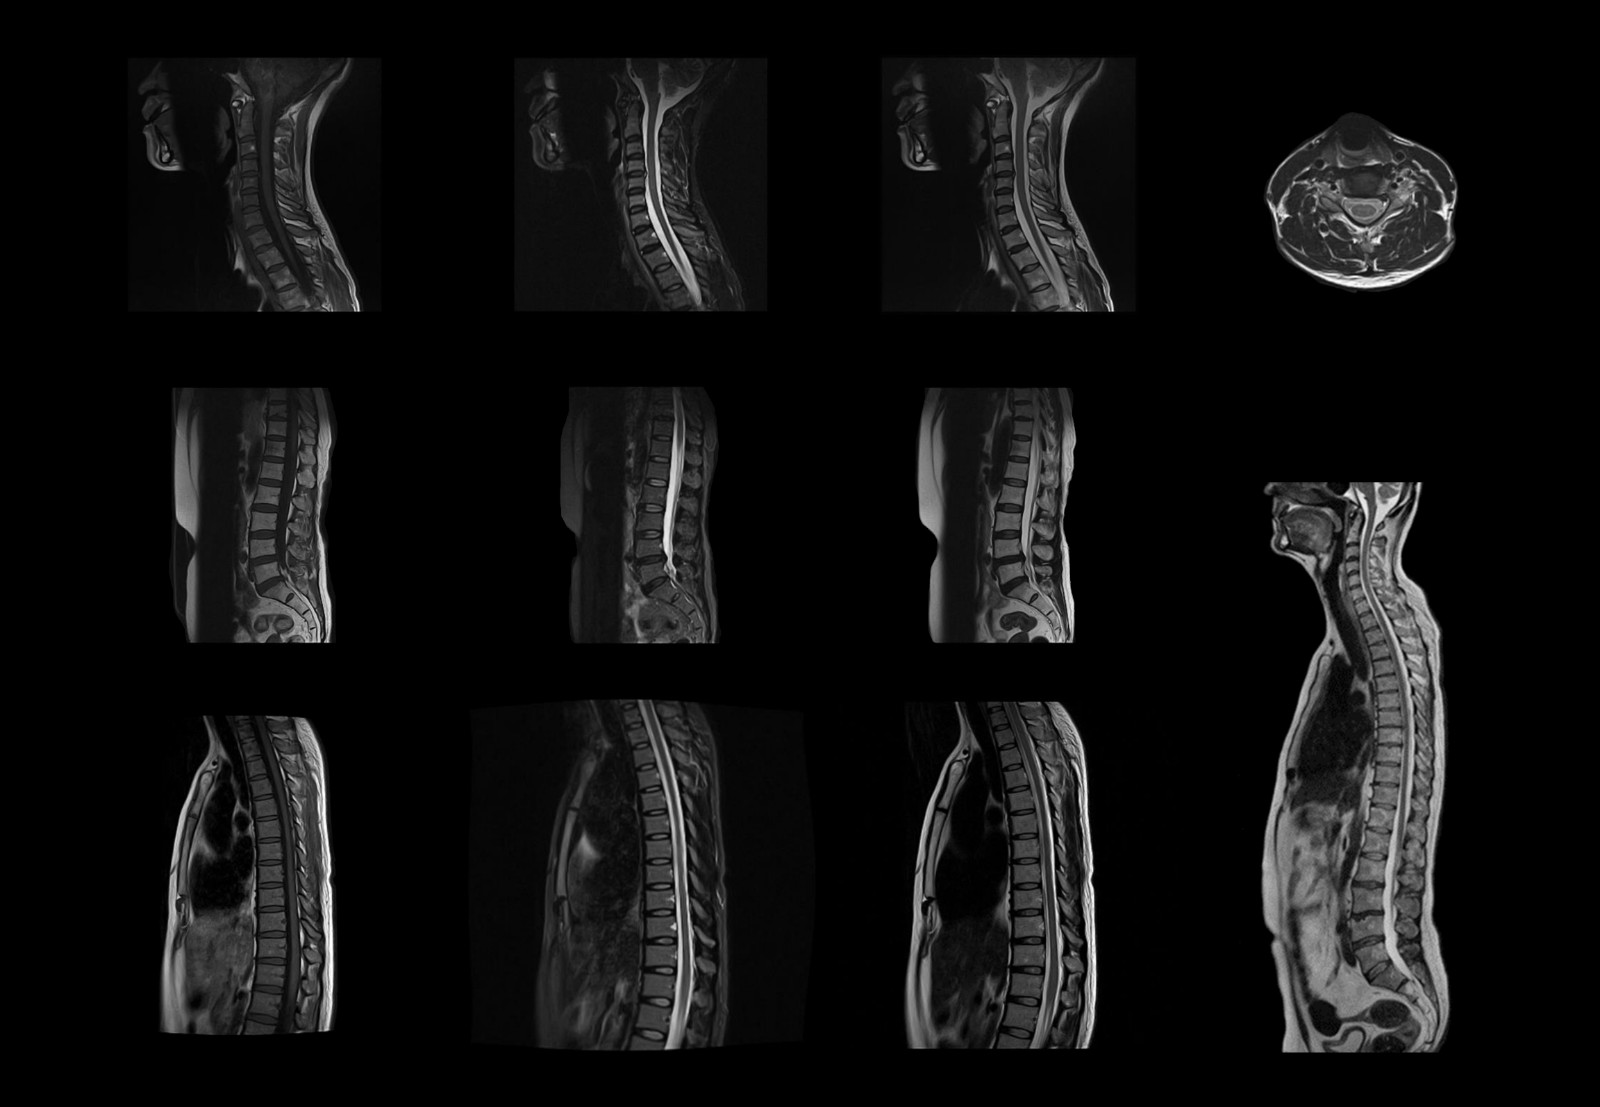

Album d'images cliniques

• Spine